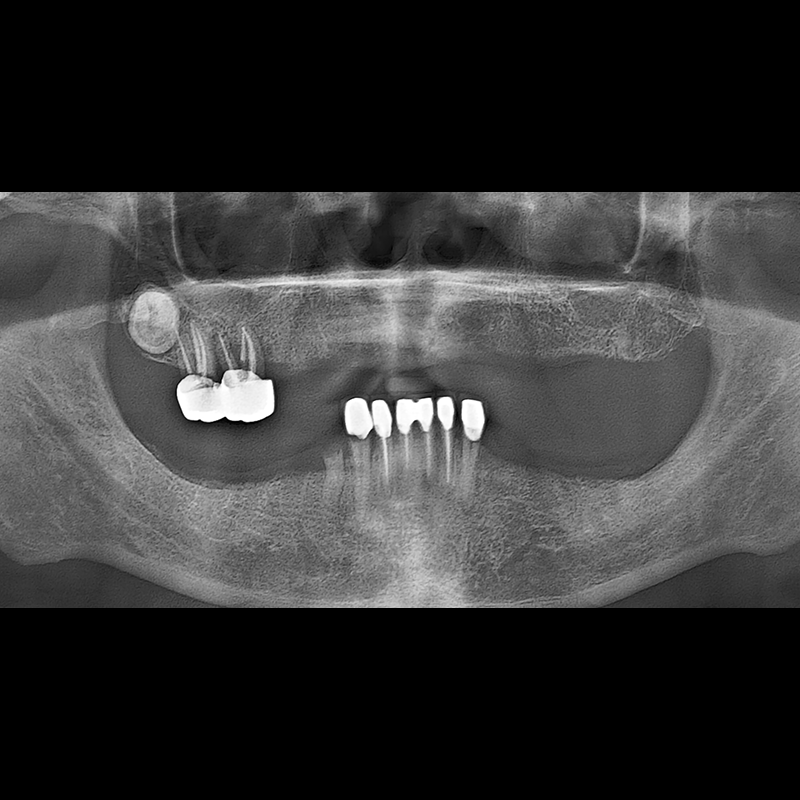

BEFORE AFTER

Implant before and after 2025.05.30

Implants were placed in the missing tooth and in the tooth position where it was difficult to save.